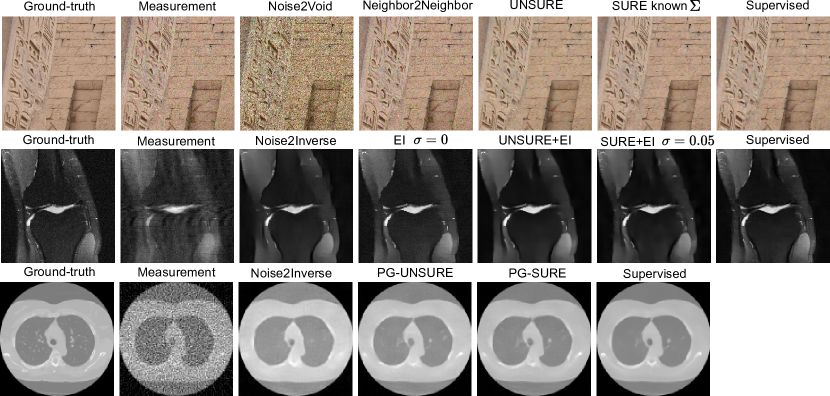

We show the performance of the proposed loss in various inverse problems and compare it with state-of-the-art self-supervised methods. All our experiments are performed using the deep inverse library (Tachella et al., 2023b). We use the AdamW optimizer for optimizing network weights 𝜽𝜽\bm{\theta} with step size 5×1045superscript1045\times 10^{-4} and default momentum parameters, and set α=0.01𝛼0.01\alpha=0.01, μ=0.9𝜇0.9\mu=0.9 and τ=0.01𝜏0.01\tau=0.01 for computing the UNSURE loss in Algorithm 1. Examples of reconstructed images are shown in Figure 5.

Refer to caption

Figure 5: Image reconstruction results for various imaging problems. Top: colored Gaussian noise on DIV2K. Middle: Accelerated magnetic resonance imaging with FastMRI. Bottom: computed tomography with Poisson-Gaussian noise on LIDC